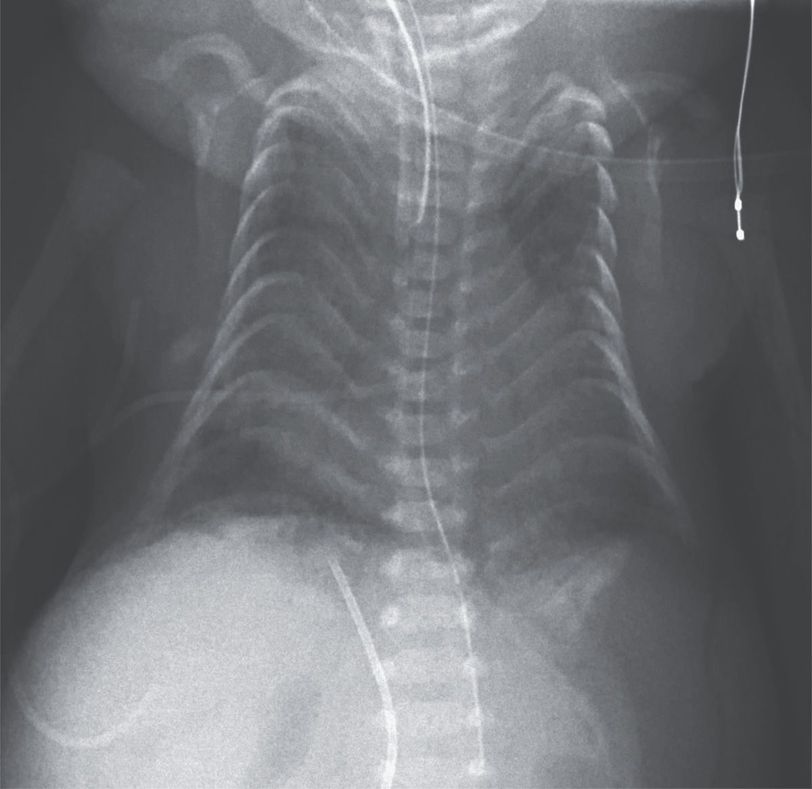

Respiratory distress developed in a male neonate immediately after birth at 28 weeks of gestation. The pregnancy had been complicated by preeclampsia, and delivery was performed by emergency cesarean section. The infant underwent intubation, and surfactant was administered through the endotracheal tube. Physical examination showed a giant omphalocele, webbed neck, and deformity of both hands. Antenatal ultrasonography at 22 weeks of gestation had shown the presence of an omphalocele and polyhydramnios. Chest radiography on the first day of life showed a narrowing of the rib cage with crowding of the ribs in a “coat hanger” appearance. On the basis of antenatal studies and the clinical presentation, a diagnosis of paternal uniparental disomy 14 was suspected. This disorder is caused by the inheritance of two copies of chromosome 14 from the father, resulting in a distinctive phenotype that includes the characteristic “coat hanger” deformity of the ribs. Genetic testing confirmed the diagnosis. After receiving ventilator support for 4 weeks, the infant died from a ruptured omphalocele and septic shock.